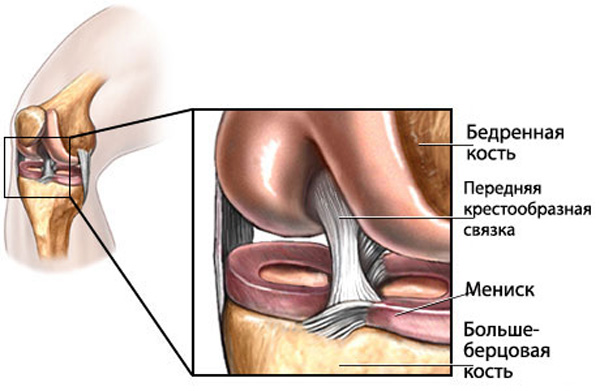

Анатомические изображения менисков и коленного сустава

Раздел: Иллюстрированные советы